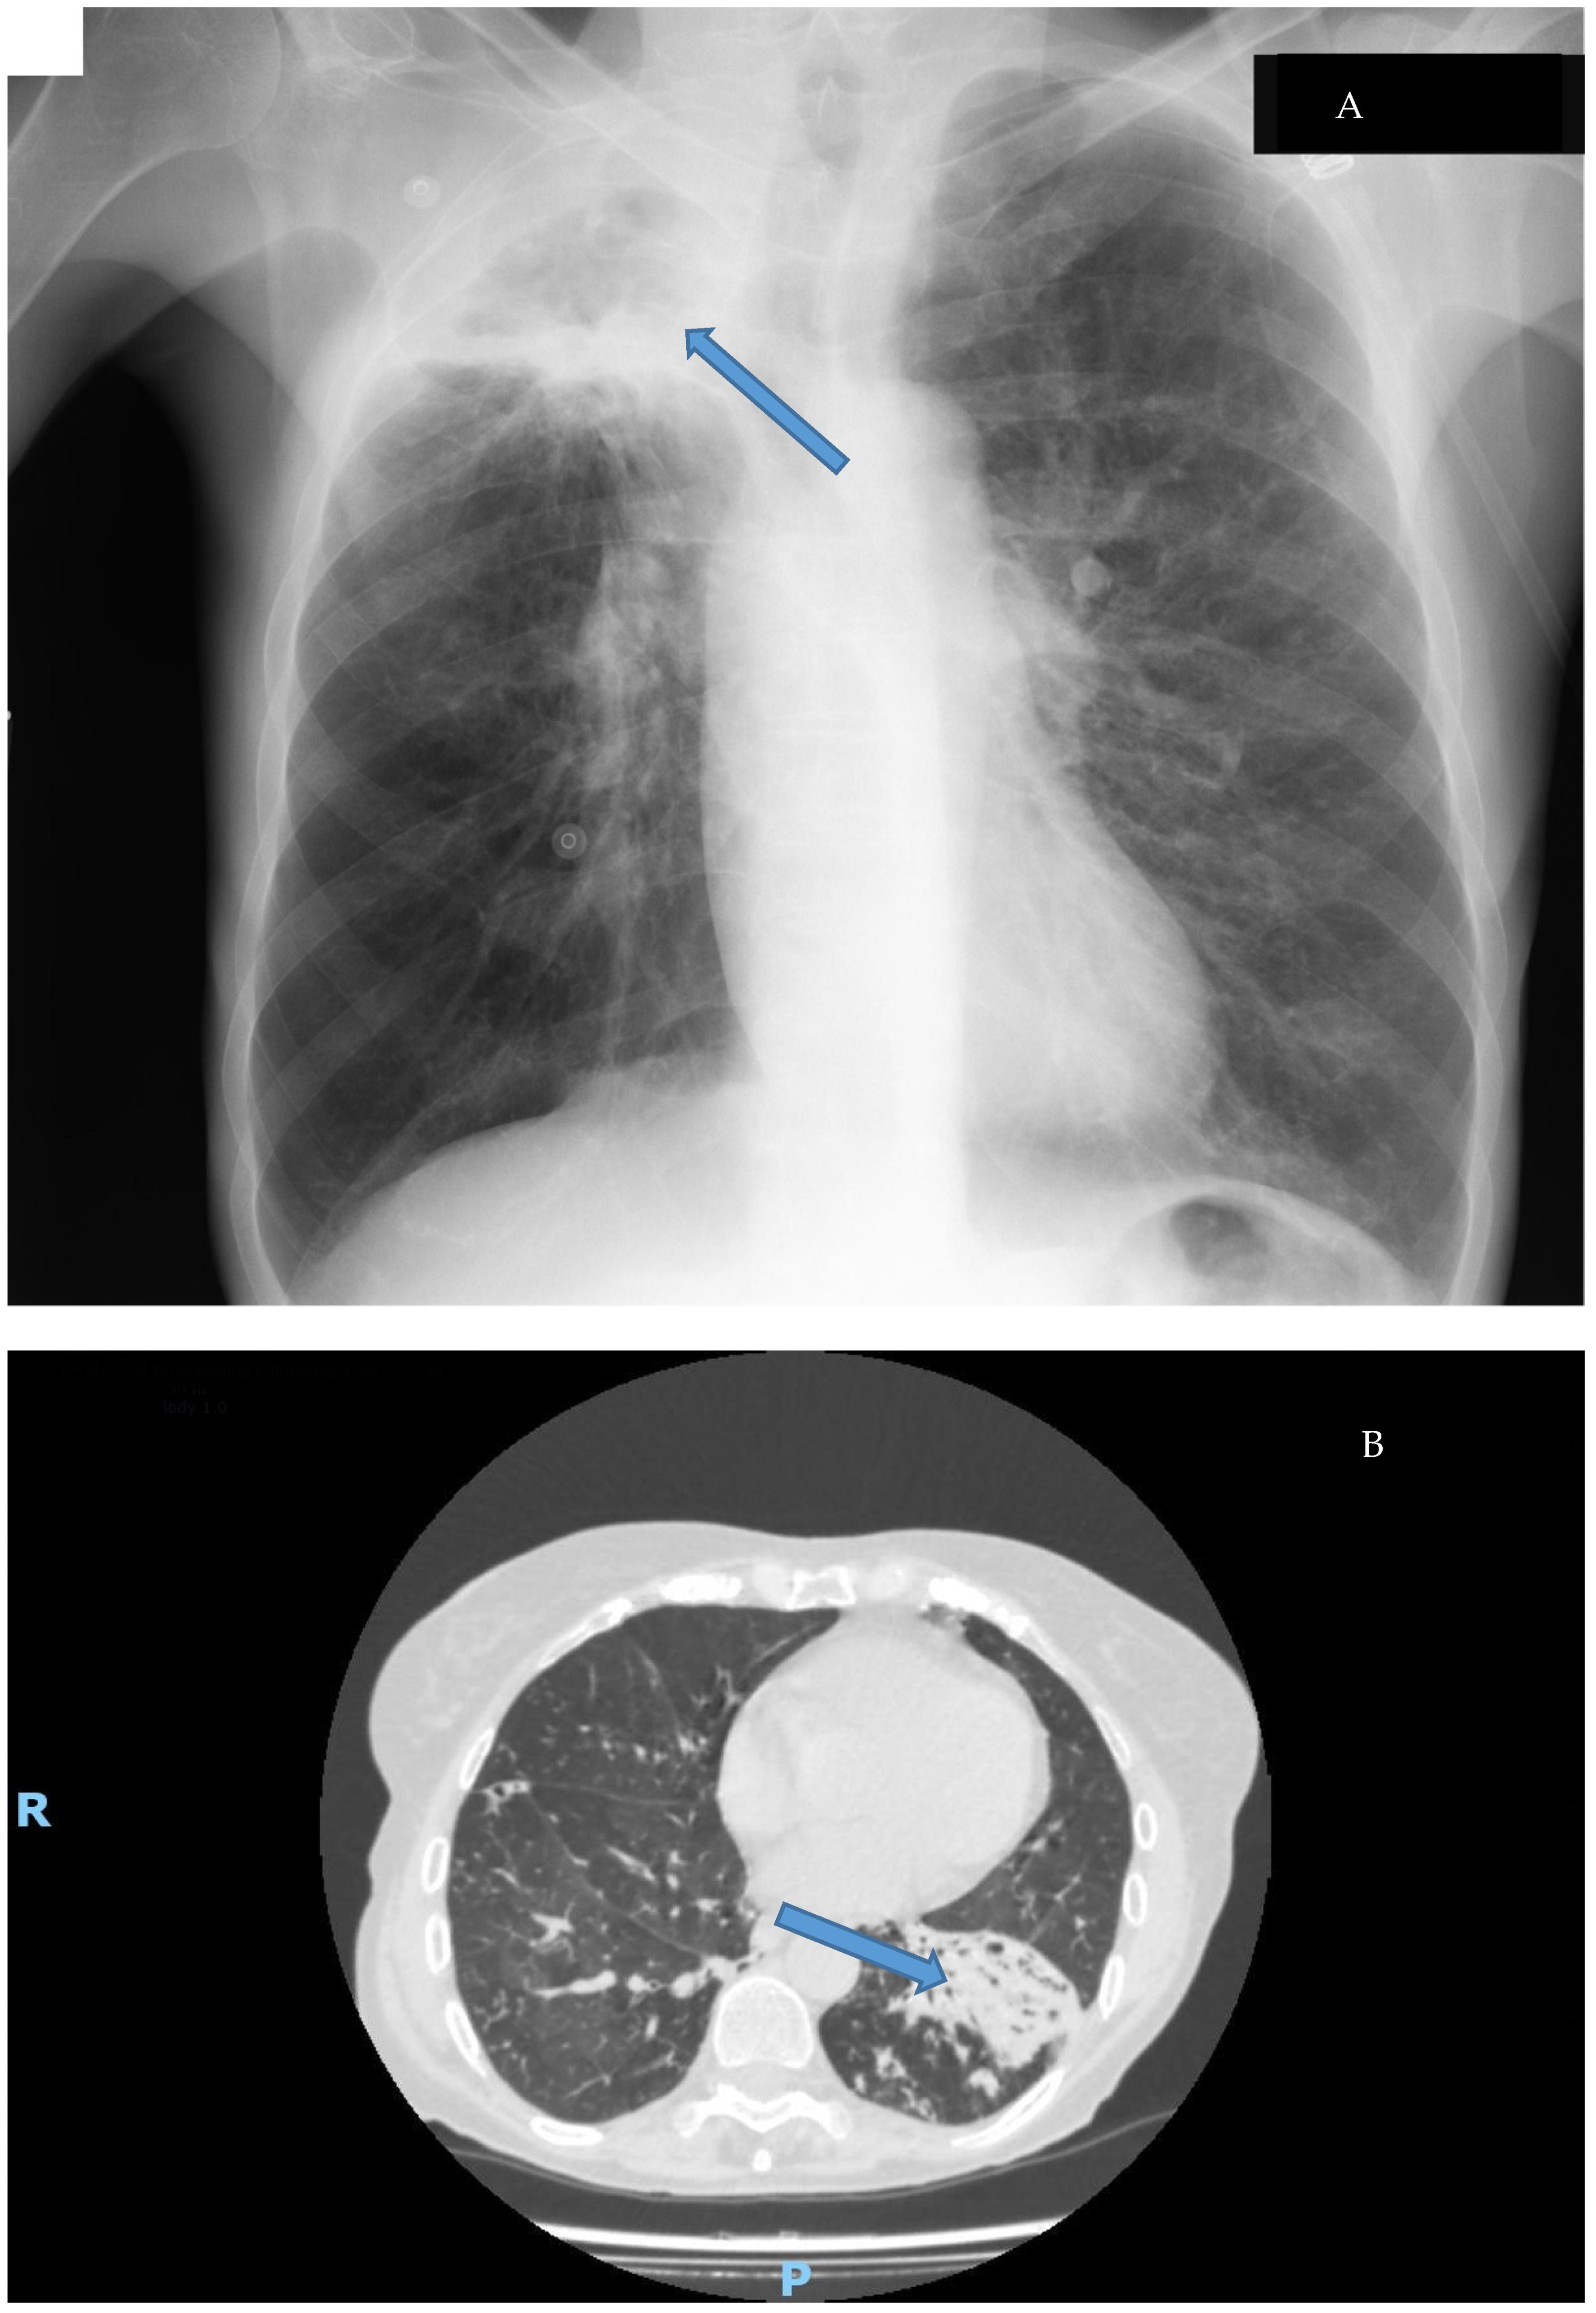

- Griffith, D.E.; Girard, W.M.; Wallace, R.J. Clinical Features of Pulmonary Disease Caused by Rapidly Growing Mycobacteria: An Analysis of 154 Patients. Am. Rev. Respir. Dis. 1993, 147, 1271–1278. [Google Scholar] [CrossRef]